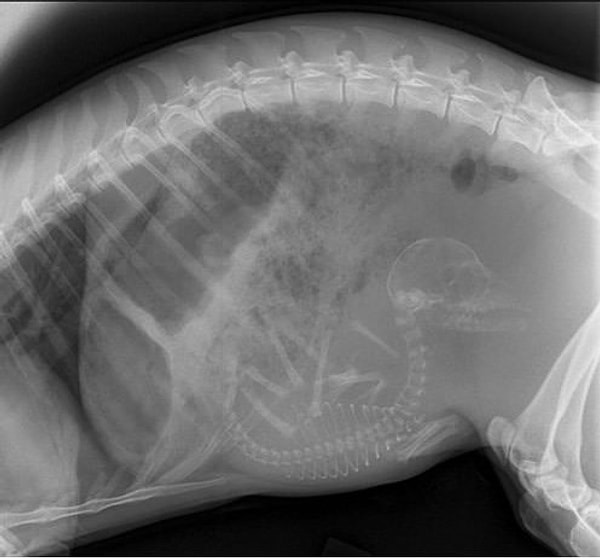

5. Кошка